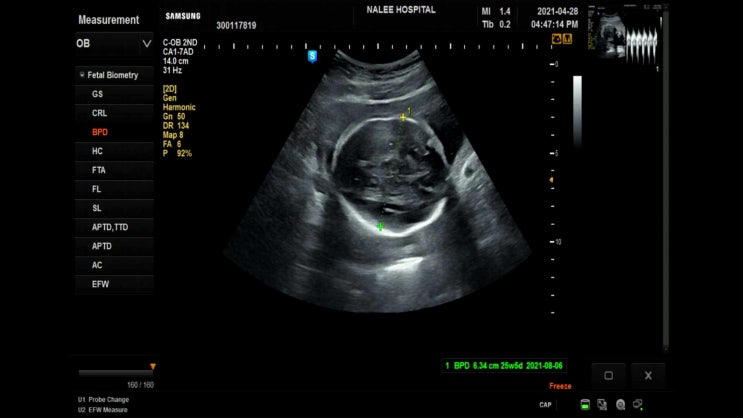

20210428 24주차 공포의 임당검사 그리고 입체초음파

어느덧 24주차라니! [21주차 이후 증상] 허리 통증이 심해짐 태동이 점점 늘어나고 강력해지는 중 변해가는...